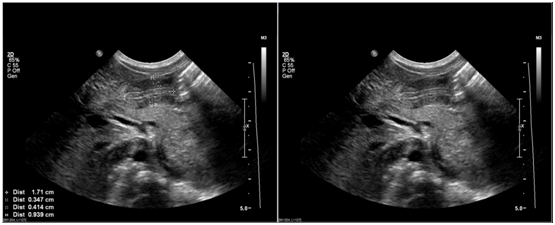

He remained relatively asymptomatic until DOL 7 after which he restarted with episodes of post-prandial non-bilious vomiting 4-5times a day, which were occasionally projectile. An ultrasonography of the abdomen on DOL 10 revealed a high normal pyloric canal length (PCL) of 14mm and a normal pyloric muscle thickness (PMT) of 2mm (Figure 1). Post prandial transmission of intraluminal content through the pylorus was mildly delayed. The radiological findings were deemed inconclusive of pyloric stenosis. Formula and breast milk were thickened. The infant began to arch his back and cry after feedings whilst he demanded frequent feeds and fed vigorously. Famotidine was started for a presumptive diagnosis of gastro esophagral reflux on DOL 11. Occasional intermittent non-bilious and projectile vomiting persisted; however, electrolytes remained normal. On physical examination visible post prandial gastric peristalsis was noted to occur starting during the first week, which became more common with increasing chronological age, but olive mass was not palpated. An upper GI series was done on DOL 17, which demonstrated holdup of ingested contrast within the stomach, though some oral contrast was visualized in the small bowel. Gastroesophageal reflux was noted up to the level of the clavicles. At this stage, evolving pyloric stenosis was suspected and a repeat abdominal ultrasonography was performed on DOL 20. Longitudinal images by sonogram demonstrated a PCL of 17mm and PMT of 3.5mm consistent with IHPS, along with a pylorus that did not distend with administration of water into the stomach (Figure 2).

Figure 1 Results of ultrasonography studies performed on day of life 10.